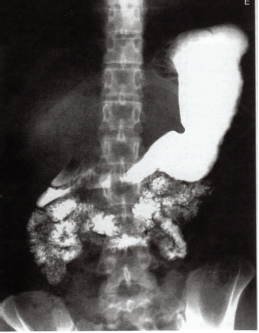

Considerando os exames radiográficos do sistema gástrico, observe a imagem a seguir e assinale a alternativa correta.

Trata-se de uma seriografia gastrointestinal superior na posição póstero-anterior com a presença do contraste à base de bário no estômago e duodeno